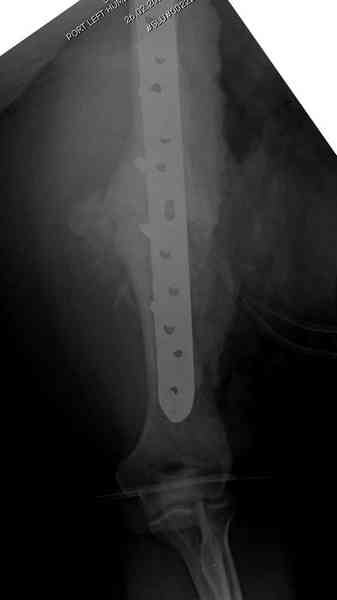

Как видно из выступлений коллег, способы фиксации

ложного сустава плеча могут быть различными, кто-то предпочитает аппаратом Илизарова (Соломин), пластинами (Волна) или интрамедуллярным гвоздем (Челноков).

Когда разбирался случай на сайте, и у нас была больная с похожей патологией, ложный сустав после поперечного перелома, леченного год назад где-то и кем-то в другом месте.

Мы не стали делать провокационный метод, который

предложил Корнеев для лечения - применение анаболических стероидов - ретаболила, из-за его бессмысленности, также не согласились с его теорией, что любая операция заблокирует суставы, а наоборот, провели жесткую фиксацию пластиной для раннего восстановления.

Первичную пластину убрали недели 6 назад из переднего оригинального доступа, и из-за подозрительности тканей вокруг пластины, решили провести реконструкцию поэтапно.

Хотя сам не стороннник применения более массивных

имплантов для плеча, но для этого случая сделали

исключение. На снимке 4А диаметр мягких ткани около 20 см, при весе больной более 135 кг, и также выступление Андрея Волны подстегнуло к применению более массивной 4.5 мм локинг пластины.